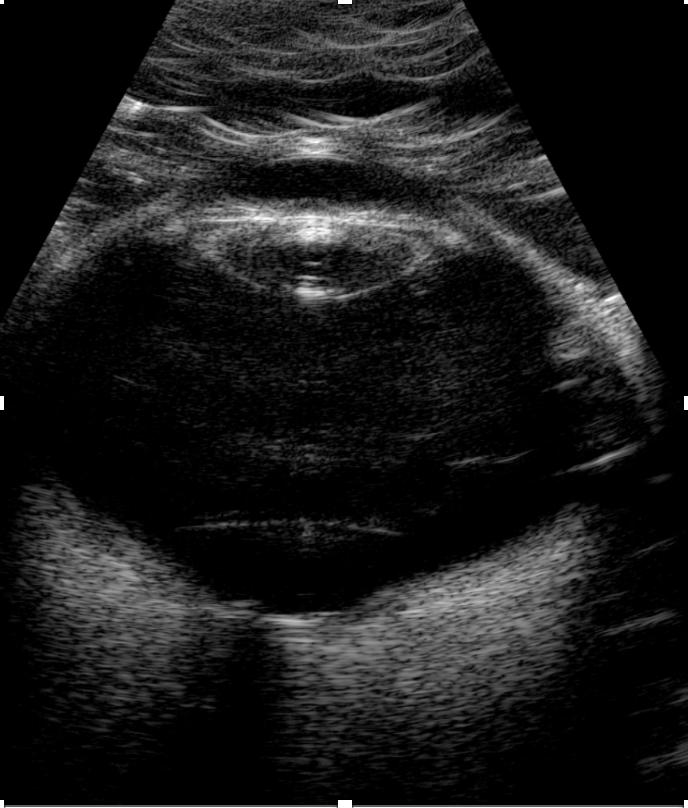

Mode B : imagerie bidimensionnelle en temps réel

Le mode B (Brillance) reconstruit une image en coupe bidimensionnelle du globe oculaire en temps réel. Chaque écho est représenté par un point lumineux dont l'intensité est proportionnelle à l'amplitude de l'écho. C'est l'examen de première intention lorsque l'examen du fond d'œil est impossible.

Technique par contact

La sonde (10 MHz) est appliquée directement sur la paupière fermée à travers un gel de couplage stérile. Le patient est en position semi-assise ou allongée. Cette technique est rapide, confortable et permet l'exploration du globe complet et de l'orbite antérieure. L'opérateur réalise des coupes standardisées en déplaçant la sonde selon différentes orientations.

Principe de l'échographie oculaire en mode B : la sonde posée sur la paupière fermée émet des ultrasons qui traversent le globe. Les échos de retour, traités par l'appareil, reconstituent une image en coupe 2D (B-scan) affichée en temps réel sur l'écran.